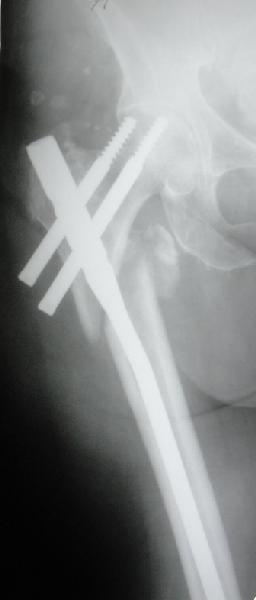

Перелом тут больше подвертельный. Нагрузка без торцевого упора на уровне перелома привела к телескопированию отломков на стержне. Ну и варус небольшой тоже свою лепту внес - если бы его не было, контактирующие латеральные стенки обоих отломков предотвратили бы укорочение, да и срослось бы за пару месяцев. А раз не срослось, упора отломков нет, более слабым местом оказались не нижние винты, а кость в головке и шейке. Так что надо было хотя бы удалить нижние винты до начала полной нагрузки.

На мой взгляд, причиной телескопирования явилось несоответствие диаметра гамма нэйл с диаметром канала подвертельного отдела бедра: обратите внимание на величину протрузии шеечного винта и величину медиализации дистального фрагмента - они одинаковы, смещение или телескопирование фрагментов происходило до того момента, пока гамма нэйл не упёрся в медиальный кортекс и образовалось пространство между латеральным

кортексом и латеральной поверхностью гвоздя.